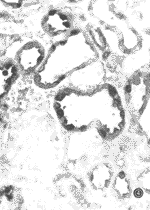

图2 肾小管上皮细胞的ET-1(原位杂交 ×400)

Fgiure 2 ET-1 in tubular epithelial cells (ISH ×400)

, 百拇医药 图3 肾小管上皮细胞的ET-1(免疫组化 ×400)

Figure 3 ET-1 in tubular epithelial cells (Immunohistochemistry ×400)

图4 再生的肾小管上皮细胞ET-1强表达(双重免疫组化 ×400)

Figure 4 ET-1 in regenerated tutular epithelial cells (double immunohistochemistry ×400)

用RIA法测得细胞培养上清中ET质量浓度分别为17.42 ng*L-1。以细胞总RNA为模板,在ET-1特异引物引导下,经RT-PCR扩增后,扩增产物为546 bp(图1)。对肾小管上皮细胞爬片进行地高辛标记的ET-1 mRNA原位杂交,结果细胞胞浆中显示明显紫蓝色阳性信号(图2)。以ET-1多克隆抗体为一抗,对培养的肾小管上皮细胞的爬片及涂片进行免疫组织化学染色,结果为强阳性(图3)。ET-1与PCNA双重免疫组化染色结果表明:实验第7、9、12天PCNA阳性的肾小管上皮细胞(即损伤及再生的肾小管上皮细胞)ET-1表达强阳性(图4),而正常及实验第1、3、5天的大鼠肾小管上皮细胞ET-1呈弱阳性。上述结果说明肾小管上皮细胞有ET-1 mRNA的表达,又有ET-1的蛋白合成与分泌,而且,损伤及再生的肾小管上皮细胞ET-1的合成明显增加。